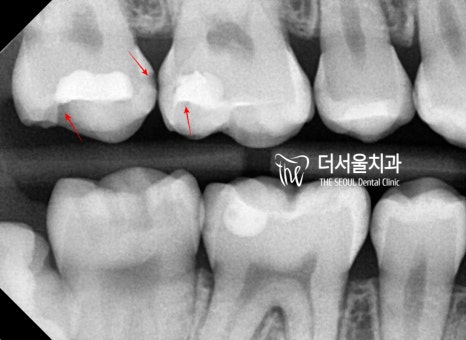

반갑습니다, 더서울의 박현준 원장입니다. 2차 우식이란 이미 병소가 생겼던 곳에 또다시 세균 감염이 일어나 우식이 생긴 것을 의미합니다. 많은